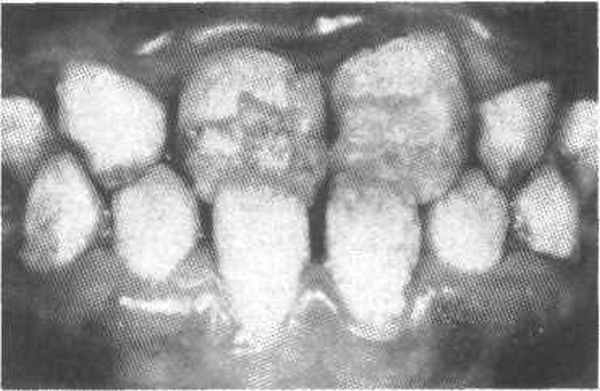

Дефекты коронок многократно пломбировались, но безуспешно. Пломбы выпадали быстро, иногда через несколько часов. У младшей сестры в 15—16-летнем возрасте были удалены четыре зуба из-за полного их разрушения. При клиническом исследовании установлено, что симптомы заболевания у сестер аналогичны, однако более выраженны у младшей сестры. Зубы имеют необычный цвет, но окраска зубов неоднородная. Цвет колеблется от серого до светло-коричневого с янтарной полупрозрачностью. У младшей сестры зубы окрашены более интенсивно, и здоровый вид у нее имеют только восьмые зубы. У старшей сестры нормальный цвет имеют верхние премоляры, а также сохранившиеся моляры (рис. 1б).

Рис. 1б. Зубы старшей сестры.

У обеих сестер более интенсивно окрашены зубы нижней челюсти. У старшей сестры зубы более крупные и имеют бочкообразную форму, у младшей бочкообразность зубов менее выраженна. Все зубы устойчивы. Имеются множественные сколы зубов. Края сколов находятся под десной, а линии сколов проходят по предполагаемым границам полостей зубов. Полости зубов облитерированы. Все участки обнаженного дентина имеют коричневый цвет, тверды и безболезненны при зондировании (рис. 3).

Рис. 3. Цвет обнаженного дентина.